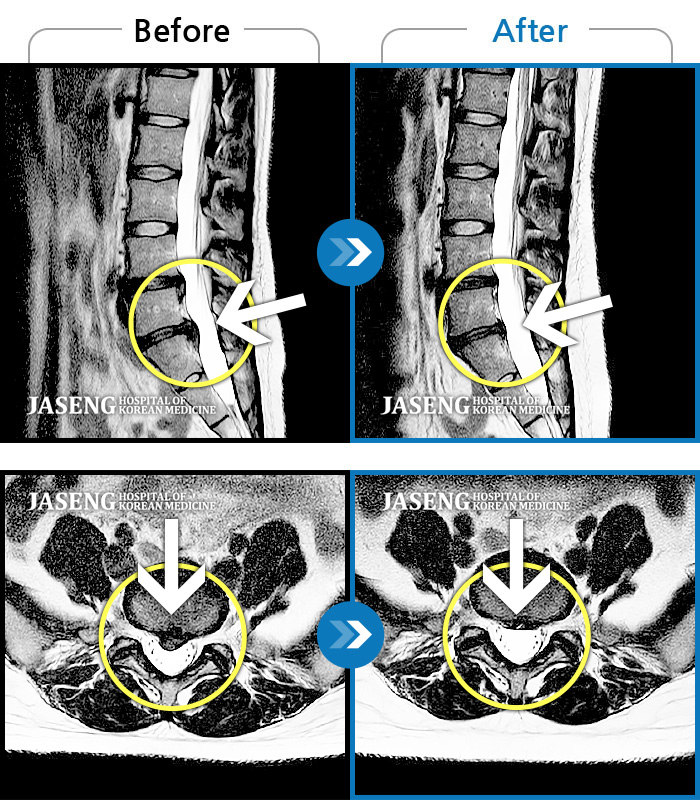

허리디스크

천안 · 윤영웅 원장

허리통증이 심해서 거동이 안돼요.

촬영시기

2021.09.13 ~ 2024.06.11

2024.06.21